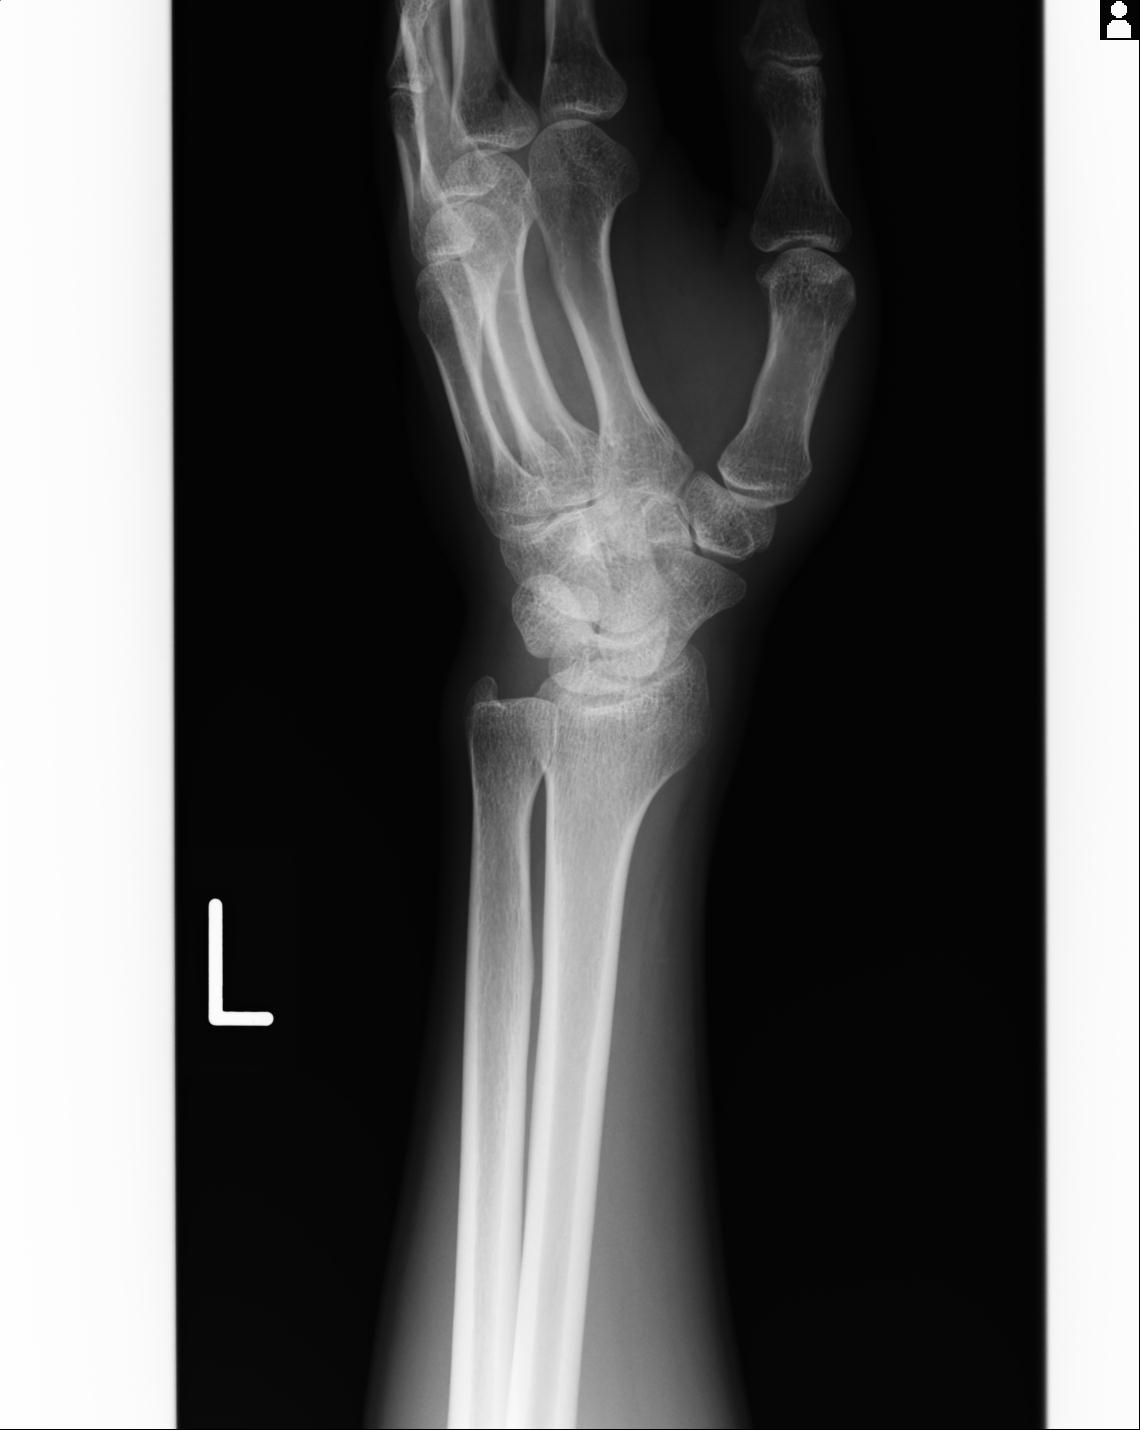

46666 1/23 両股正面+軸と右手関節 2R 76歳女性 右橈骨遠位端

46666 1/28 両股正面+軸と 1/26 右手関節 2R 76歳女性 右転子部骨折